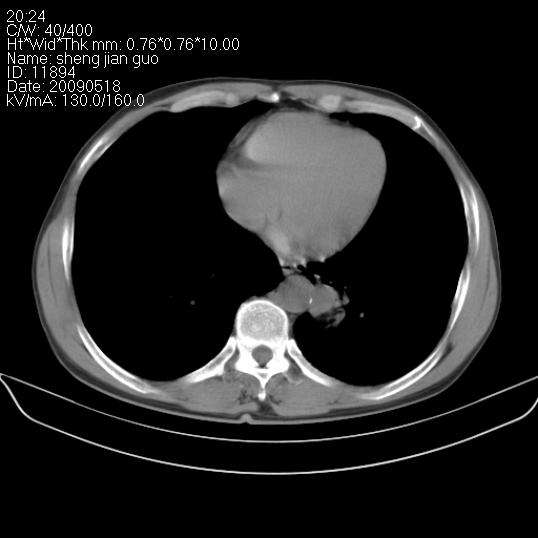

以下是引用zjzjr在2009-5-19 17:25:00的发言:[br]支持楼主考虑,另左肺下叶阻塞性炎症。

以下是引用zhao_bin2008在2009-5-19 17:48:00的发言:[br]支持左肺下叶周围型肺癌并阻塞性肺炎。

以下是引用zsl6918在2009-5-20 7:10:00的发言:[br]左侧中心型肺癌!